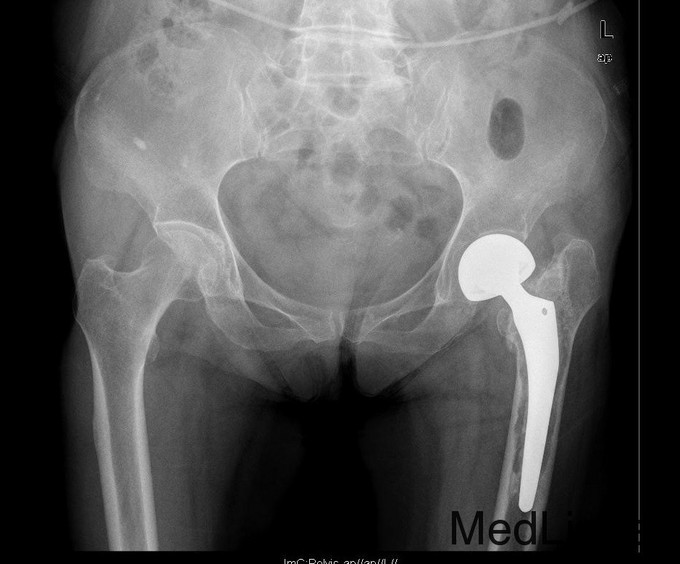

查体:专科:左髋部后外侧陈旧手术瘢痕,左髋关节前方压痛、无轴向叩击痛阴性,无大转子叩击痛,双下肢感觉及血运均正常。双下肢肌力V级。动量:右髋内外旋诱发疼痛,屈曲90度疼痛。外旋明显滚动试验阴性,左髋4字试验阳性。双下肢等长。左髋关节屈90°,伸0°,外展40°,内收20°,内旋30°外旋10°。右髋关节屈120°,伸直0°,外展40°,内收20°,内旋30°外旋30°。 辅助检查:2010-12-08 ESR 6.0mm/h,2011-01-04外院CRP8.5mg/l(参考范围0-10mg/l)X线示左双动股骨头置换术后,假体松动、下沉,髓腔内可见骨水泥影。近端干骺端骨质明显缺损。髓腔内侧皮质形态不规则。

诊断:左双动股骨头置换术后假体松动、下沉、股骨骨缺损(PaproskyII型) 治疗:患者在全麻下左双动股骨头假体取出+同种异体骨植骨+左全髋关节翻修术,术后予以抗炎(二联)+抗凝+镇痛+护胃+补液等治疗,并予以抗骨质疏松药物

出院时左髋可屈曲90°,伸直0°,外展30° 讨论: 1、髋臼侧是否置换关键看什么? 2、Paprosky分型? 3、高龄患者行骨科大手术围手术期应着重注意哪些方面?( 体力、肺部感染、液体量与心功能、营养与饮食、锻炼与下肢深静脉血栓~~~~~) 4、假体柄的选择有何要求? 5、术后1天与术后3月的片子有何差别,试分析原因